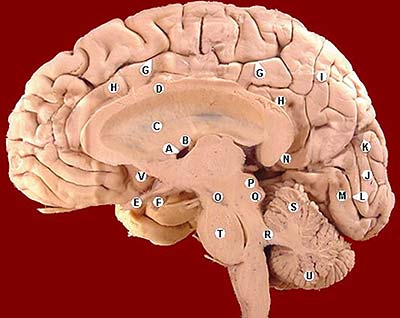

Hace solo tres meses publiqué un post de esta serie vinculada a cerebro y género, El tálamo, en el que aludía al símil culinario que tan sugerente es en relación con la investigación didáctica de las diferentes estructuras cerebrales: “En las nueces, almendras y castañas, como símbolos del cerebro, está el secreto. Algo importante “se cocina” todos los días en nuestra cabeza. Es más, en cada segundo vital”. También seguía utilizando estos criterios en el análisis del hipotálamo, la ciruela pequeña: “Hace tiempo comencé a trabajar en la construcción de inteligencia creadora que fortalezca el conocimiento de la mujer y de su estructura cerebral para ayudar a comprender mejor las igualdades y diferencias de género, con la ilusión de que el conocimiento del cerebro de las otras, de los otros, de lo que verdaderamente nos une a lo largo de millones de años, la inteligencia, sea una fuerza motriz para remover conciencias de género, enmarcadas en el respeto del conocimiento mutuo. Poco a poco avanzo en la anatomía del cerebro, a través del lenguaje, de la divulgación científica de las estructuras cerebrales que nos pueden hacer más libres porque comenzamos a saber y justificar por qué somos y nos comportamos de forma igual o diferente, sabiendo que el “secreto está en la masa” gris y blanca del cerebro (doscientos mil millones de posibilidades diferentes de ser y estar) cuando se asientan en determinadas estructuras”.

Hoy, vamos a agregar un ingrediente más, en este peculiar programa de cocina cerebral, una estructura similar a un guisante (algunos científicos hablan del formato de pera muy pequeña ó de San Juan), con un peso de 0.5 gramos, que se denomina científicamente glándula pituitaria (también conocida como hipófisis, “crecimiento inferior”) y que se aloja en un espacio óseo, la silla turca, del hueso esfenoides, situada en la base del cráneo, en la fosa cerebral media, que conecta con el hipotálamo a través del tallo pituitario o tallo hipofisario. La etimología es sumamente curiosa para comprender anatómicamente esta microestructura de extraordinaria importancia en las mujeres y hombres, por este orden. Pituitaria significa que contiene o segrega pituita, del latín “pituita”: secreción, fluido, moco, flema, formando parte de la medicina tradicional junto a los tres “humores” restantes: sangre, bilis amarilla y bilis negra. Es una superestructura del sistema endocrino dado que ejerce un control férreo sobre ocho glándulas endocrinas que explicamos a continuación.